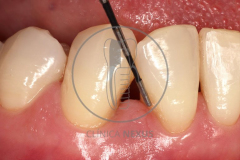

Tratamiento de defectos periodontales infraóseos en sector antero-inferior empleando gel de amelogeninas (Emdogain®) en combinación con un aloinjerto óseo (Biobank®). Paciente de 64 años, sin problemas médicos de relevancia, que presenta una periodontitis leve generalizada, pero asociada a presencia de defectos óseos verticales profundos a nivel de los espacios interdentales entre los caninos y los incisivos laterales inferiores. Tras la pertinente fase higiénica, se llevó a cabo una cirugía periodontal regenerativa, en la que, tras eliminar el cálculo subgingival (factor causal), se empleó una combinación de amelogeninas con un aloinjerto, para promover la regeneración tisular del periodonto perdido. Las imágenes clínicas y radiológicas, al año de seguimiento, reflejan un resultado terapéutico óptimo, con regeneración completa del tejido periodontal y mejora del pronóstico de los dientes involucrados.